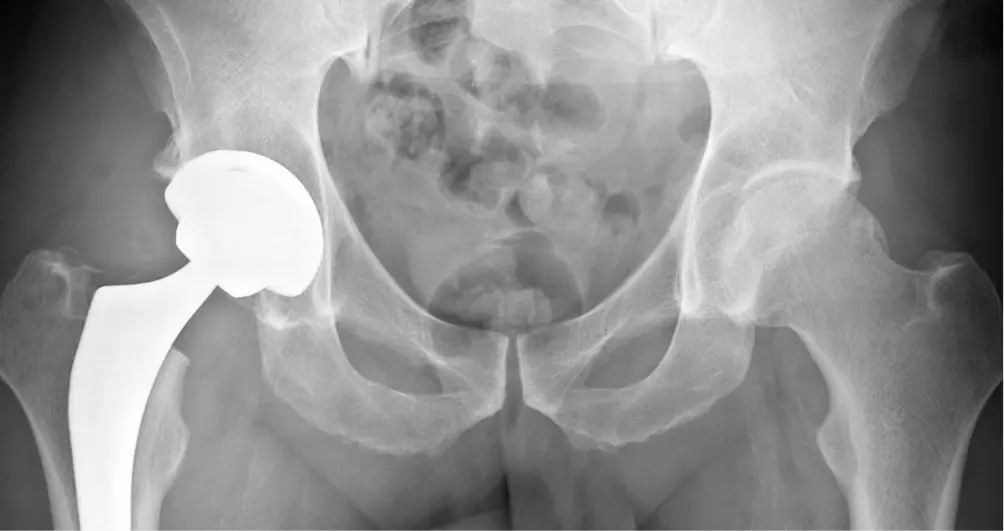

Parlons des articulations synoviales du genou et de la hanche propres à la marche et à tous nos déplacements quotidiens. La hanche et les genoux, au même titre que les autres articulations du corps humain, possèdent de nombreuses structures et de substances qui leur permettent de conserver leur mobilité et de fonctionner correctement.

Certes, l’apparition des douleurs sont liées aux conditions météorologiques caractéristiques de l’automne mais la raison est souvent due au mauvais état des articulations elles-mêmes et le groupe musculaire y correspondant. Que ce soit par excès de poids, d’usure naturelle ou suite à une blessure, vous souhaitez vous soulager au mieux, voir recouvrer sa mobilité intégrale.

L’activité physique a deux propriétés intéressantes pour la personne souffrant d’arthrose : elle a une action antalgique ; elle facilite la réduction de l’excès pondéral chez les personnes en surcharge (surpoids ou obésité).